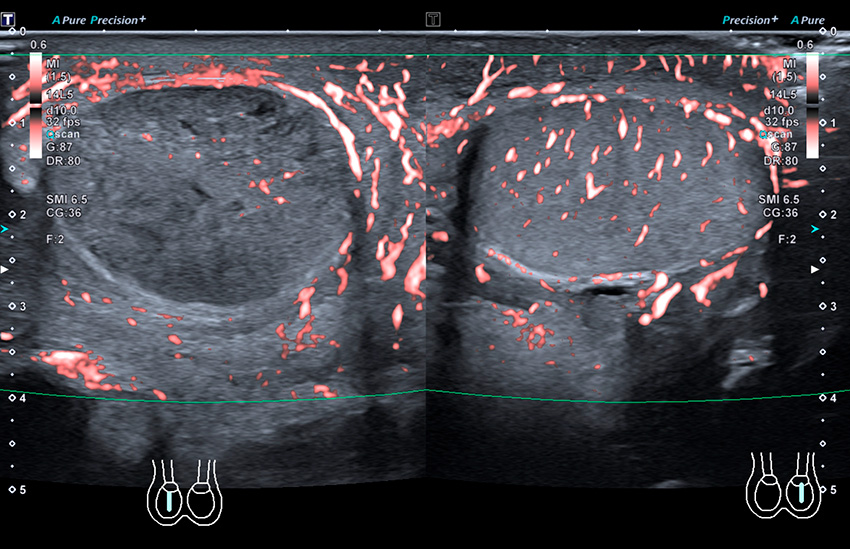

Epididymit. Högersidig epididymit där inferiora delen av epididymis är svullen, hyperemisk med omgivande retning (till vänster i bild) jämfört med kontralaterala sidan, som är normal. Den klassiska bilden är hyperemi och hyperperfusion av epididymis, som eventuellt kan vara förstorad. Observera att man vid torsion/intermittent torsion kan se liknande bild i tidigt skede.